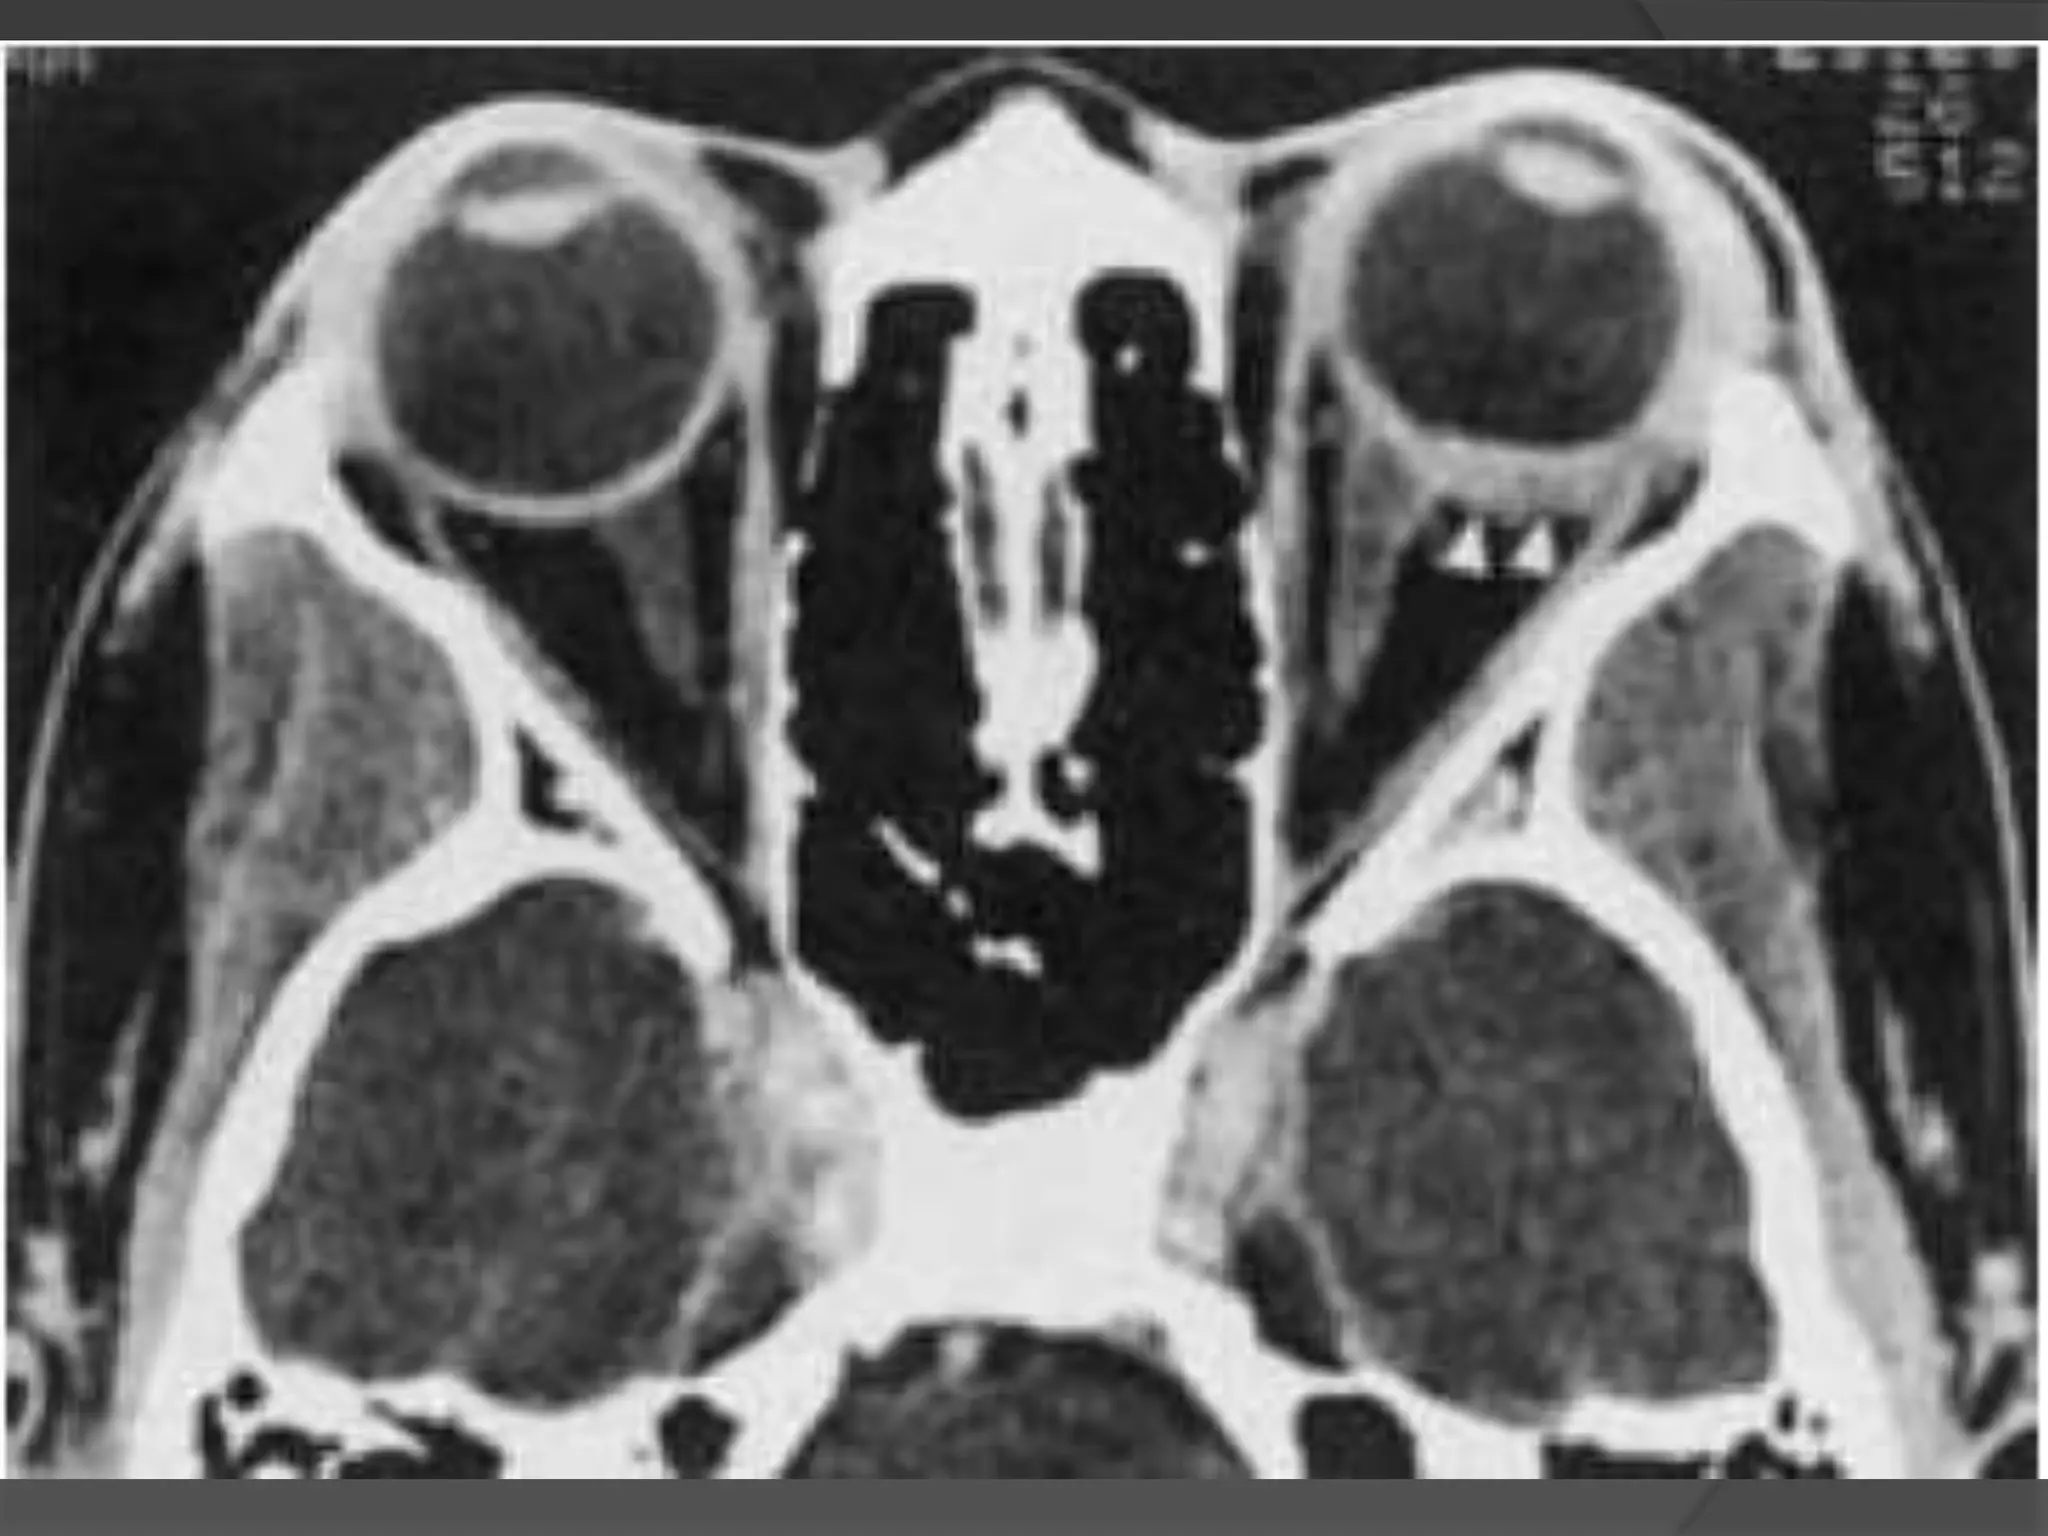

• #26 Retinoblastoma. A, Leukokoric left eye (whitish papillary reflex). B, Axial CT scan shows a large calcified intraocular mass (M). Note the noncalcified component (arrowhead). C, Axial T1WI shows a relatively hyperintense infiltrative mass (arrows). D, Axial T2WI shows a hypointense infiltrative mass (M). Note the extension along the temporal aspect of the globe (arrows).